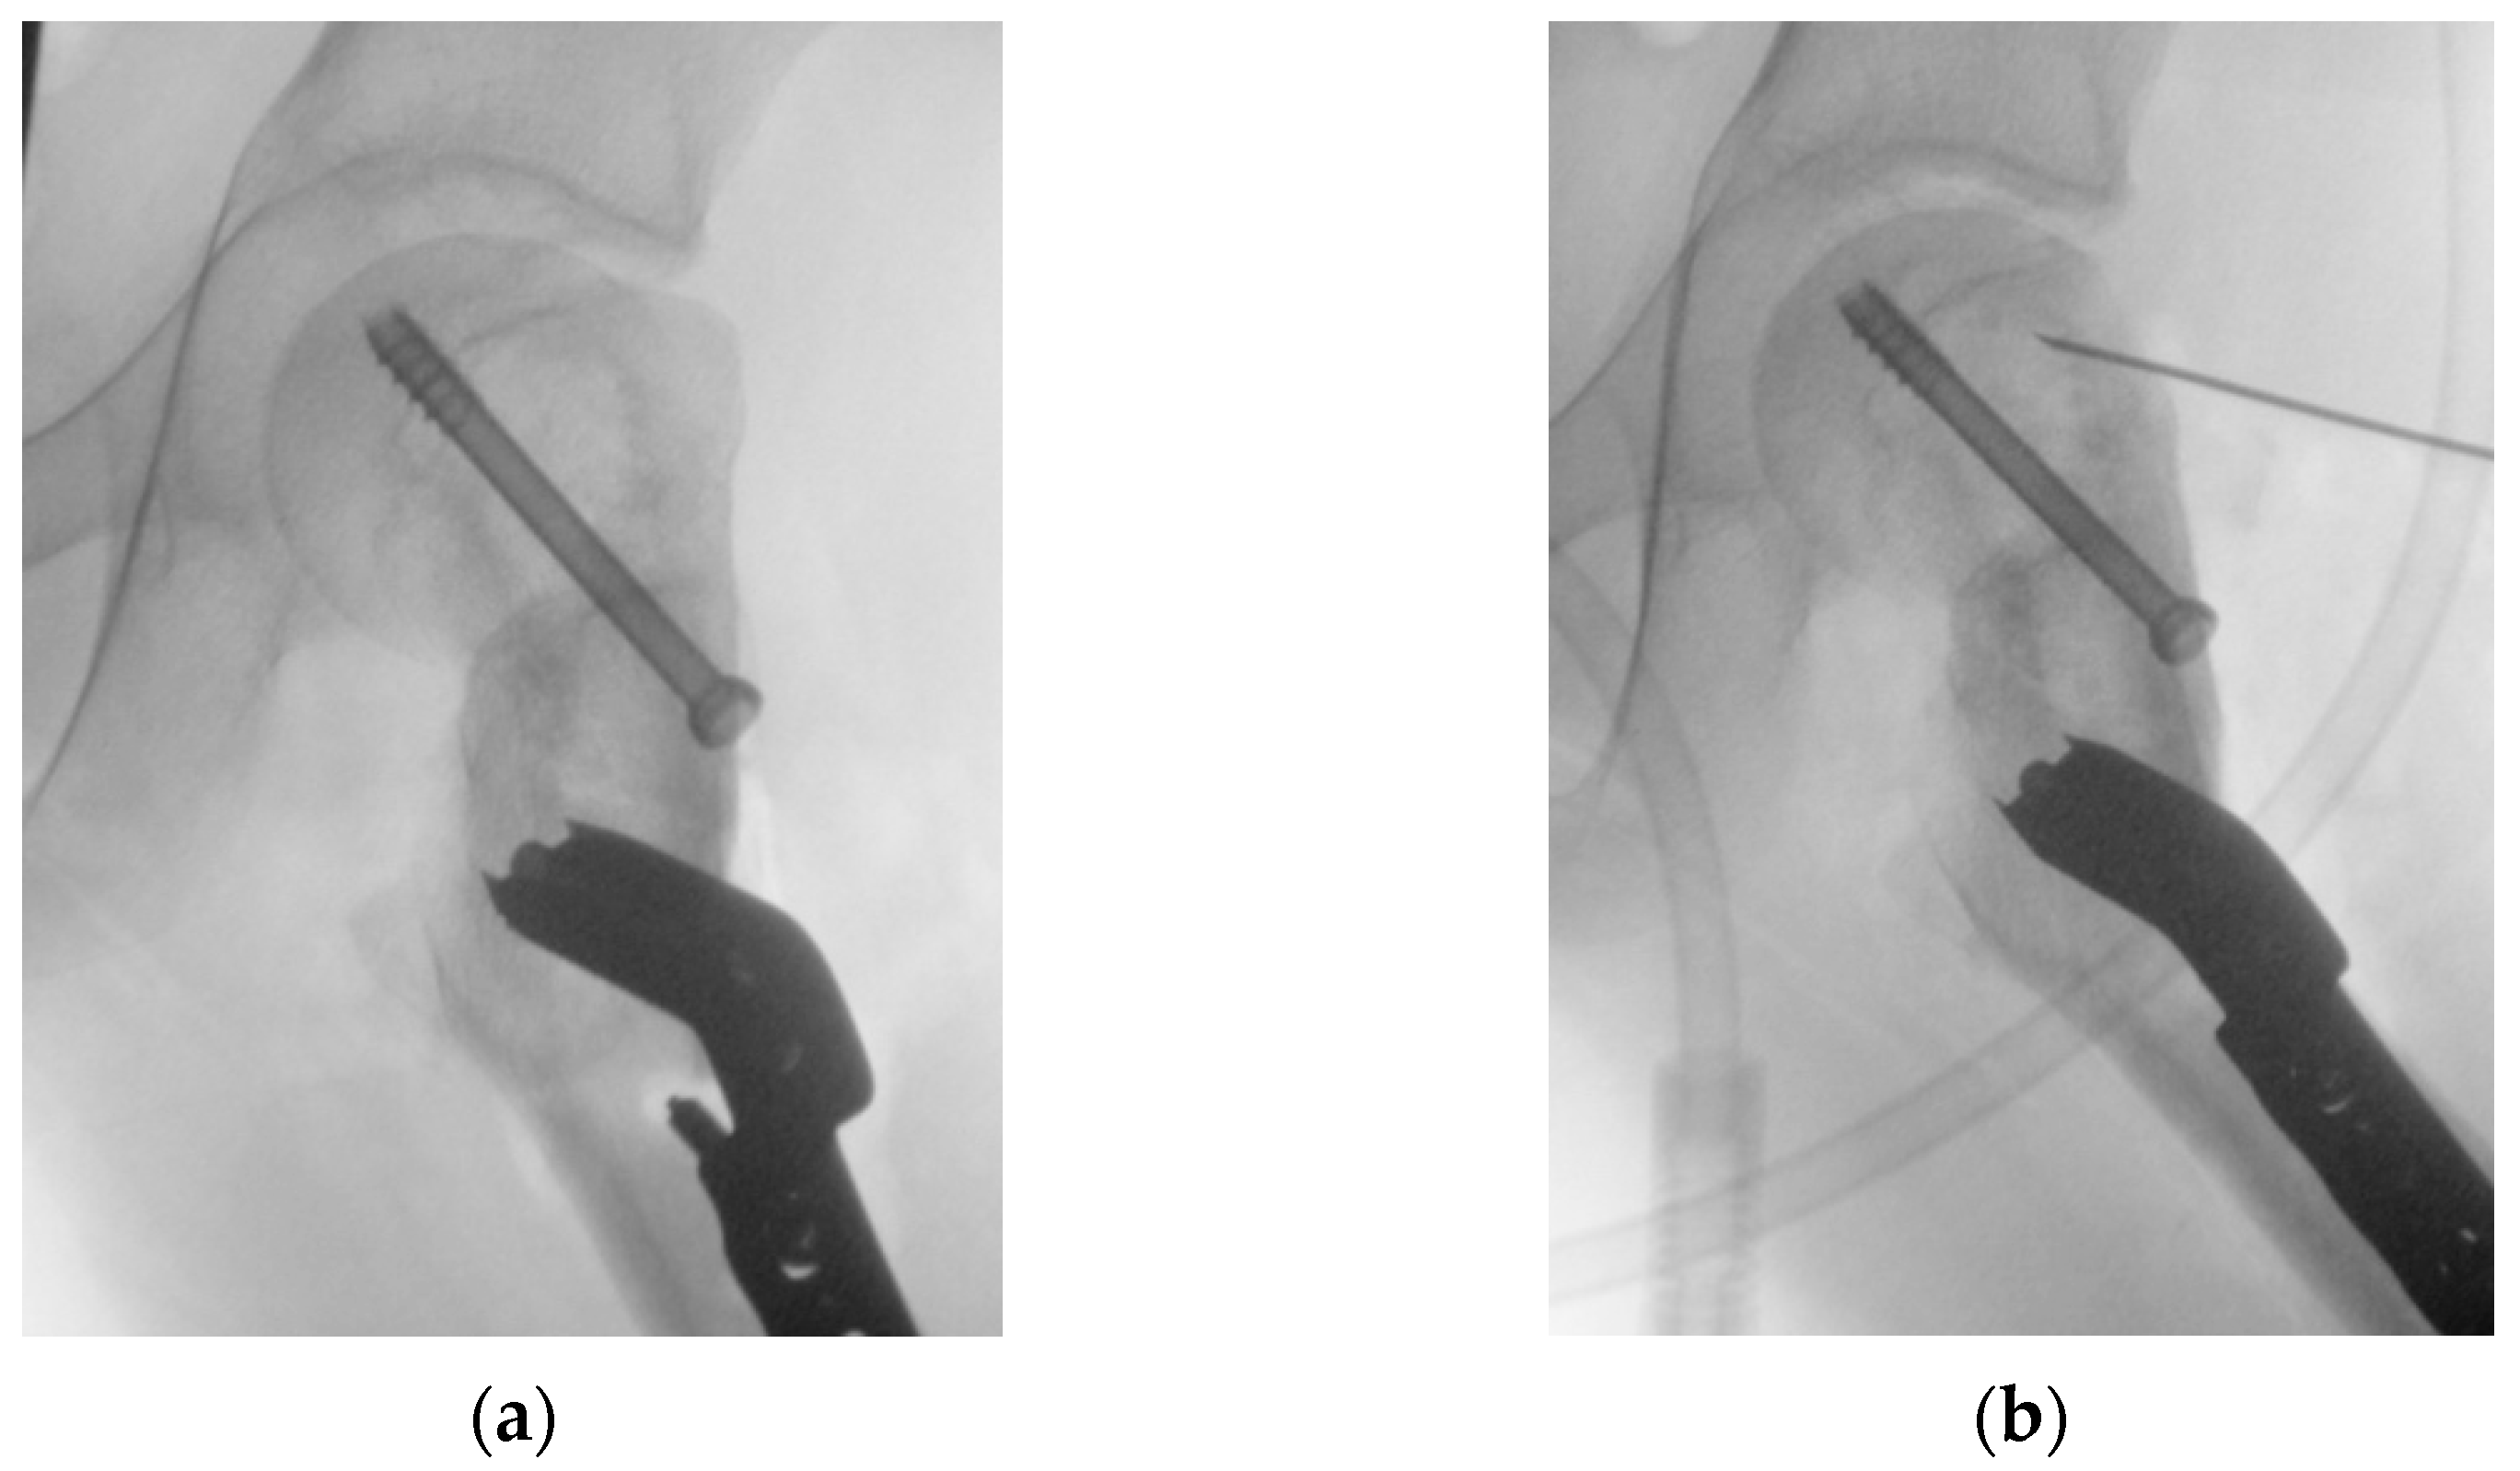

2.1. Virtual Surgical Planning and Design of 3D-Printed Cutting Guide

2.2. Surgical Procedure